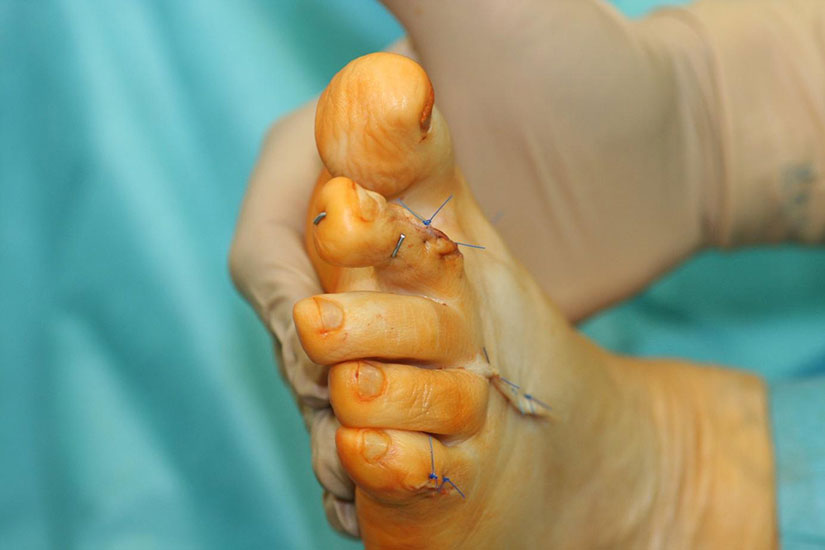

Die vorbereitenden Operationsschritte werden im Abschnitt „PIP-Arthrodese mit K-Draht-Fixierung“ in den Abbildungen 1.1 bis 1.7 beschrieben.

• regelmäßiger Verbandwechsel in den ersten beiden Wochen, Entfernung der Hautfäden nach zwei Wochen

• Eine schmerz- und schwellungsadaptierte Belastung ist direkt postoperativ in einem Verbandschuh mit harter Sohle möglich. Die Thromboseprophylaxe erfolgt bis zur Vollbelastung.